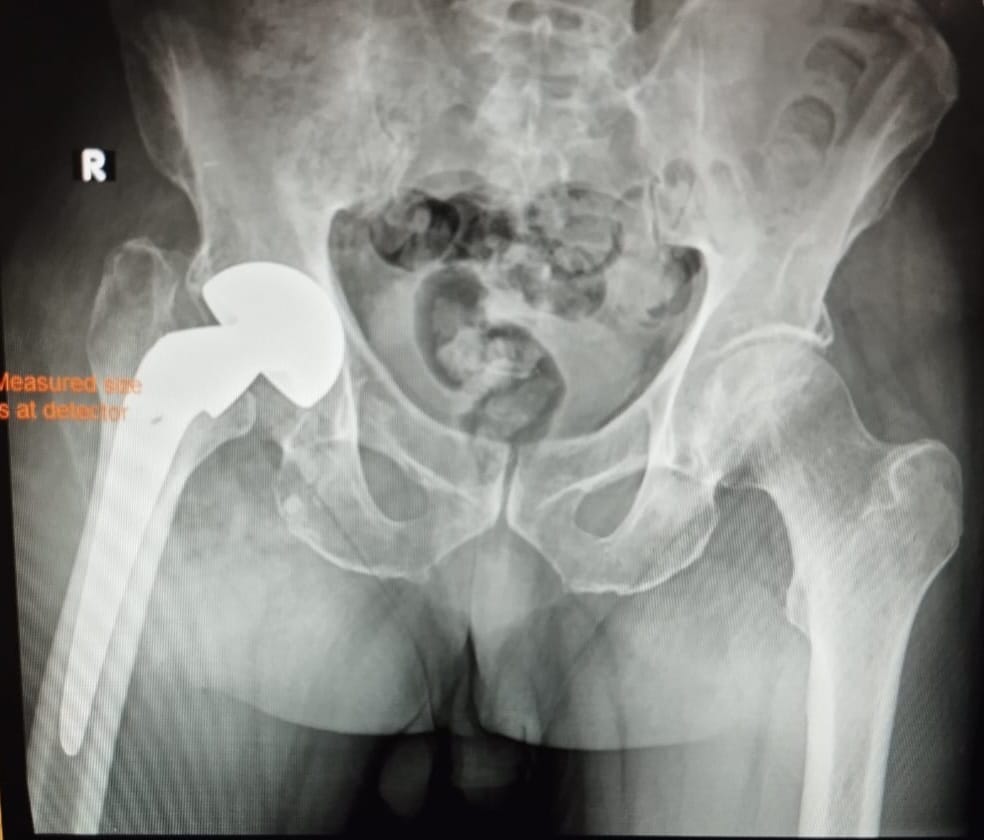

Regular follow-ups and X-rays monitor implant position and bone healing. Immediate contact with your doctor is necessary if you notice swelling, severe pain, redness, or drainage.

Revision hip surgery typically lasts around two hours. The surgeon removes all or part of the old implant and replaces it with a new one. In severe infection cases, surgery may be staged: first removing the implant to treat infection, then replacing it later.

The procedure may involve special implants if bones are weak or fractures are complex. Your surgeon will discuss these options and explain the expected outcome.